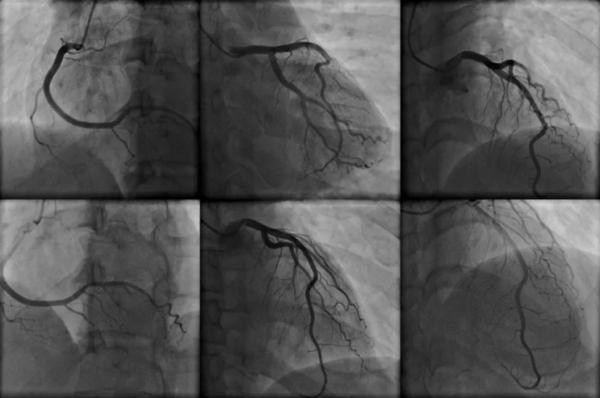

據北京清華長庚醫院張萍主任介紹,冠狀動脈造影是診斷冠心病的一種常用且有效的方法,是一種有創診斷技術。

檢查時,醫生會將一根細細的導管插入到患者的主動脈裡,透過導管向主動脈注入造影劑,造影劑沿血管流動,使X射線可以顯示出血管及心臟的形態。

冠狀造影十分可靠,但也存在一定風險,如果患者的病情已經非常嚴重,在檢查時可能刺激誘發心絞痛,這也讓很多人誤以為這是一項“要命”的檢查。冠狀動脈造影是診斷冠心病的“金標準”,對於以下幾類人來說,是必須進行的。